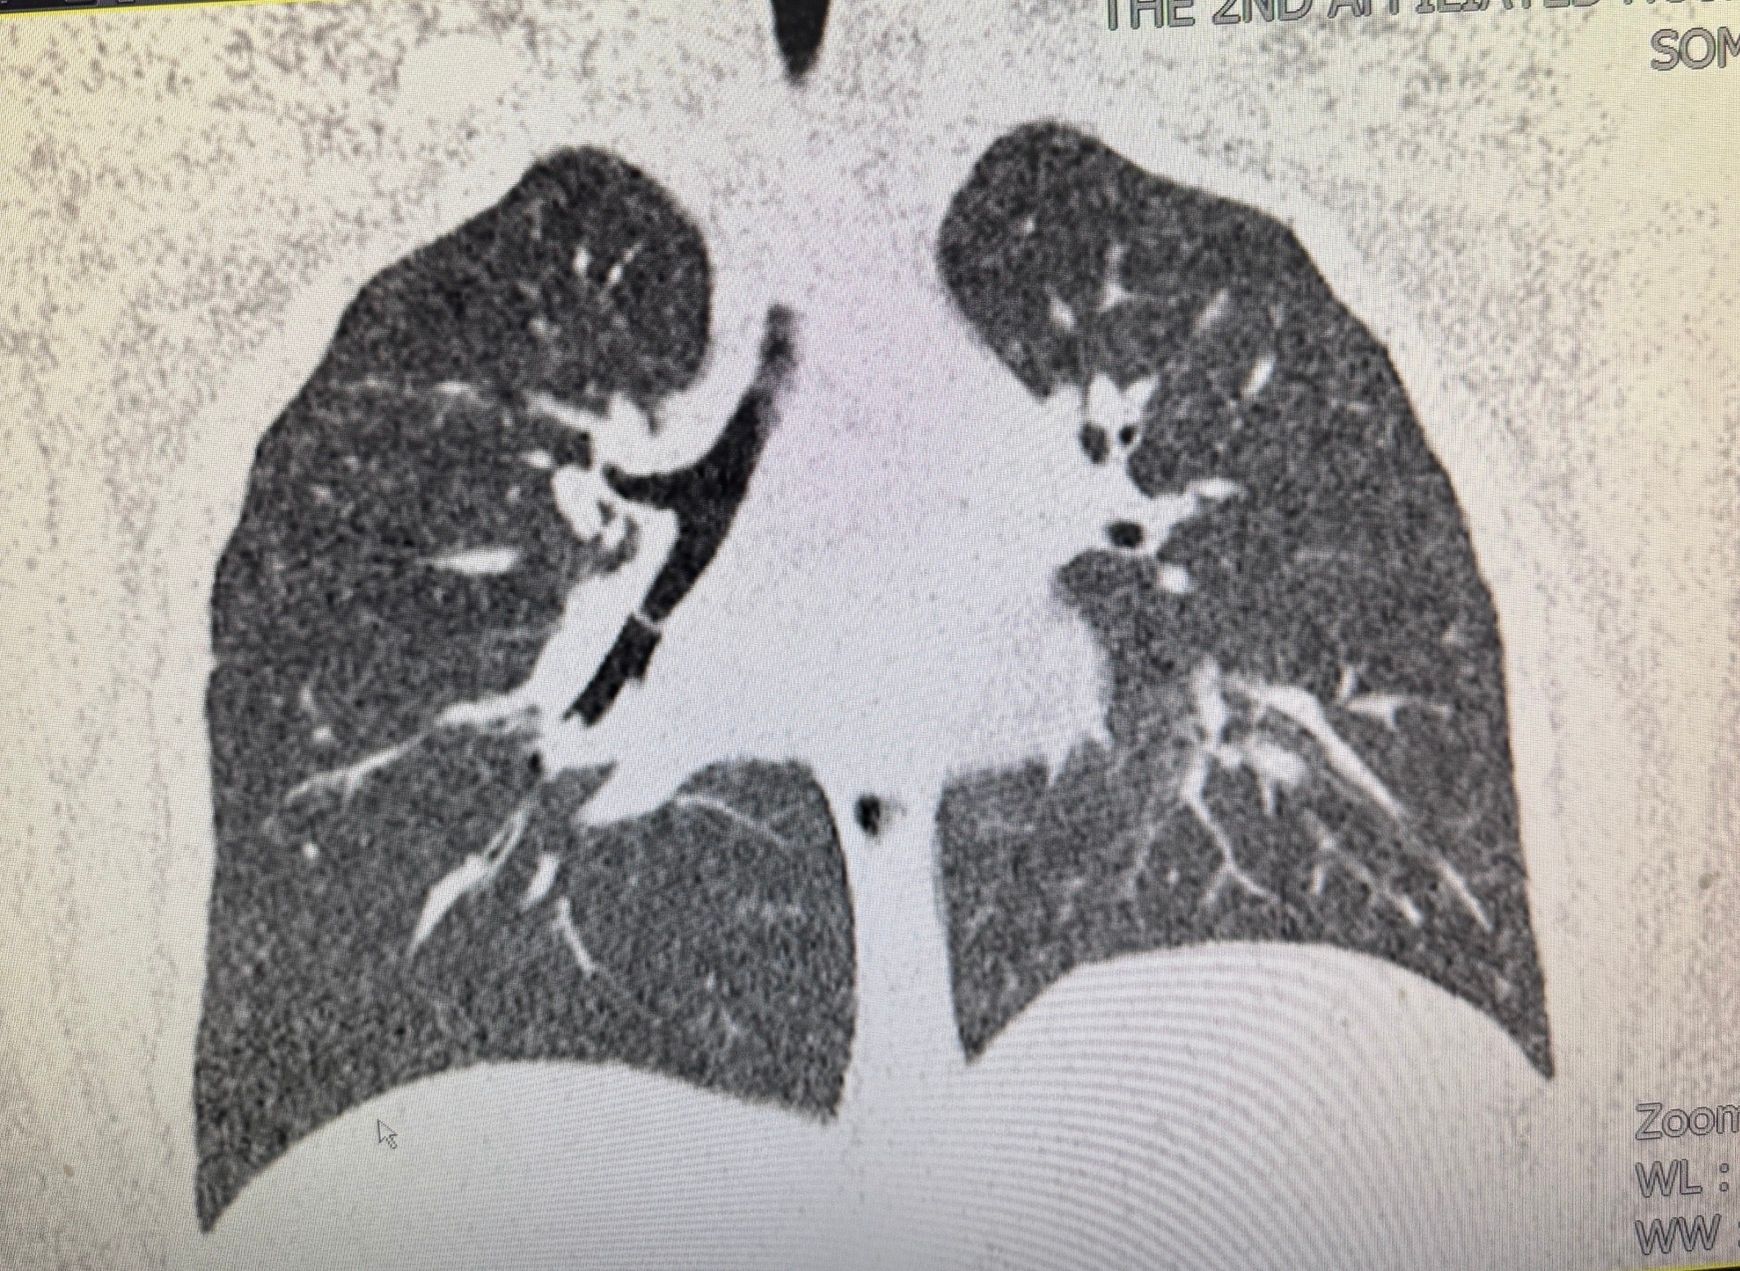

一场与时间赛跑的生命救援就此展开。值班医生张璐瑶、折宁宁立即查看患儿,兰兰呼吸急促,阵发性咳喘,听诊右肺中下叶呼吸音明显减弱,推测为右侧支气管异物。气管三维重建CT证实,一枚圆柱形异物嵌顿于右侧支气管中下叶开口处,伴右肺中叶、下叶肺不张。接到汇报后,耳鼻喉科胡娟副主任迅速组织急救,分析病情:呼吸道异物是我科常见急症,但该患儿吸入的笔帽外壁完全贴合支气管壁,内壁光滑短小,不利于钳夹,且一端完全封闭,造成气道机械性阻塞,支气管腔内负压形成,随呼吸运动负压逐渐加重,不利于笔帽松动向外拉出;因此,经气管镜钳夹异物向外取出的过程较为困难,可能造成张力性气胸或窒息,危及生命。胡娟副主任向家长介绍病情,请家长提供与吸入异物相同的笔帽,以筛选合适器械,模拟手术过程。同时请麻醉科、小儿内科、小儿外科紧急会诊,耳鼻喉科值班团队实施心电监护及吸氧支持,紧急完善各项术前检查。根据家长提供的笔帽,多学科共同制定手术预案,准备不同型号气管镜、异物钳、取石网篮、Nd.Yag激光等,以备在笔帽封闭端或内壁打孔,方便异物钳夹持。